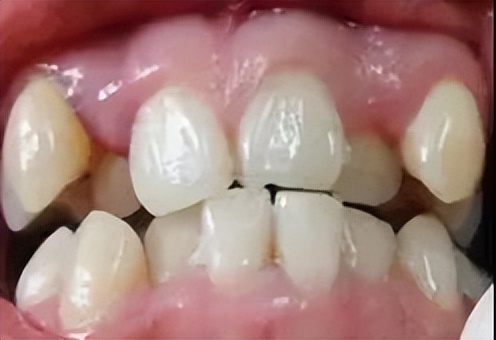

2.埋伏牙还会影响整排牙齿的排列,挤歪其他的牙齿会造成咬合紊乱异常。

3.位于前牙区的埋伏牙会对平时的面型美观有影响,甚至还是影响发音,尤其是对于心智未发育的未成年人的心理造成不良影响。